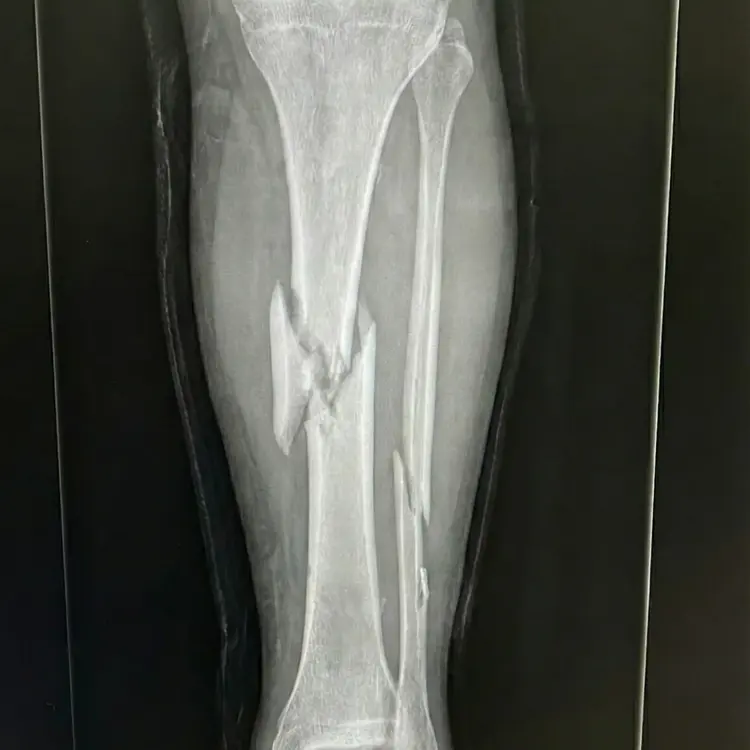

Ele tem fraturas graves nas duas pernas. Tá com pinos externos segurando os ossos no lugar. Não consegue sentar, não consegue se virar na cama. E o motorista que causou isso? Fugiu e depois disse que não tem dinheiro pra pagar nada.

O ortopedista foi direto: são 40 dias pra operar, senão os ossos calcificam na posição errada e a recuperação vira outra coisa. A fila do SUS? Oito meses. Não dá pra esperar.